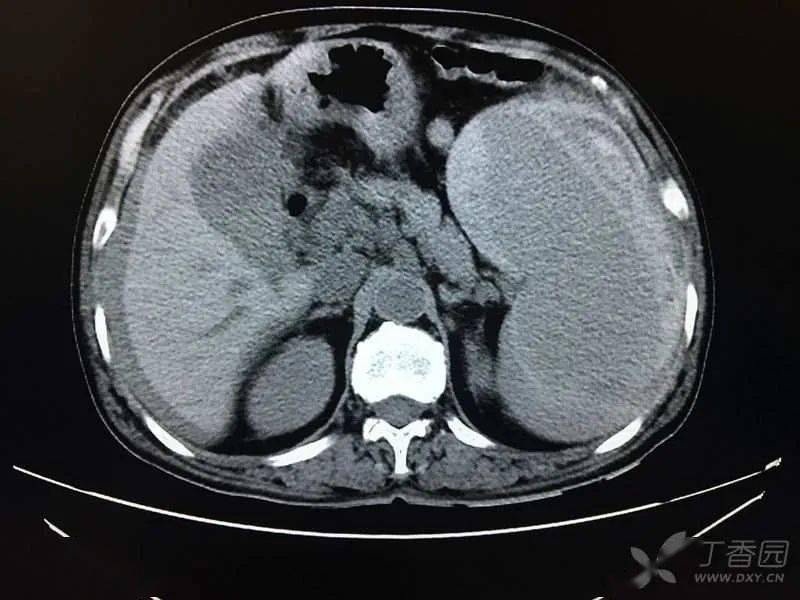

两张片子对比,最明显的改变是脾脏周围有异常混杂密度影,肝周积液,又

上腹可见游离气体,肝周积液,脾周积液